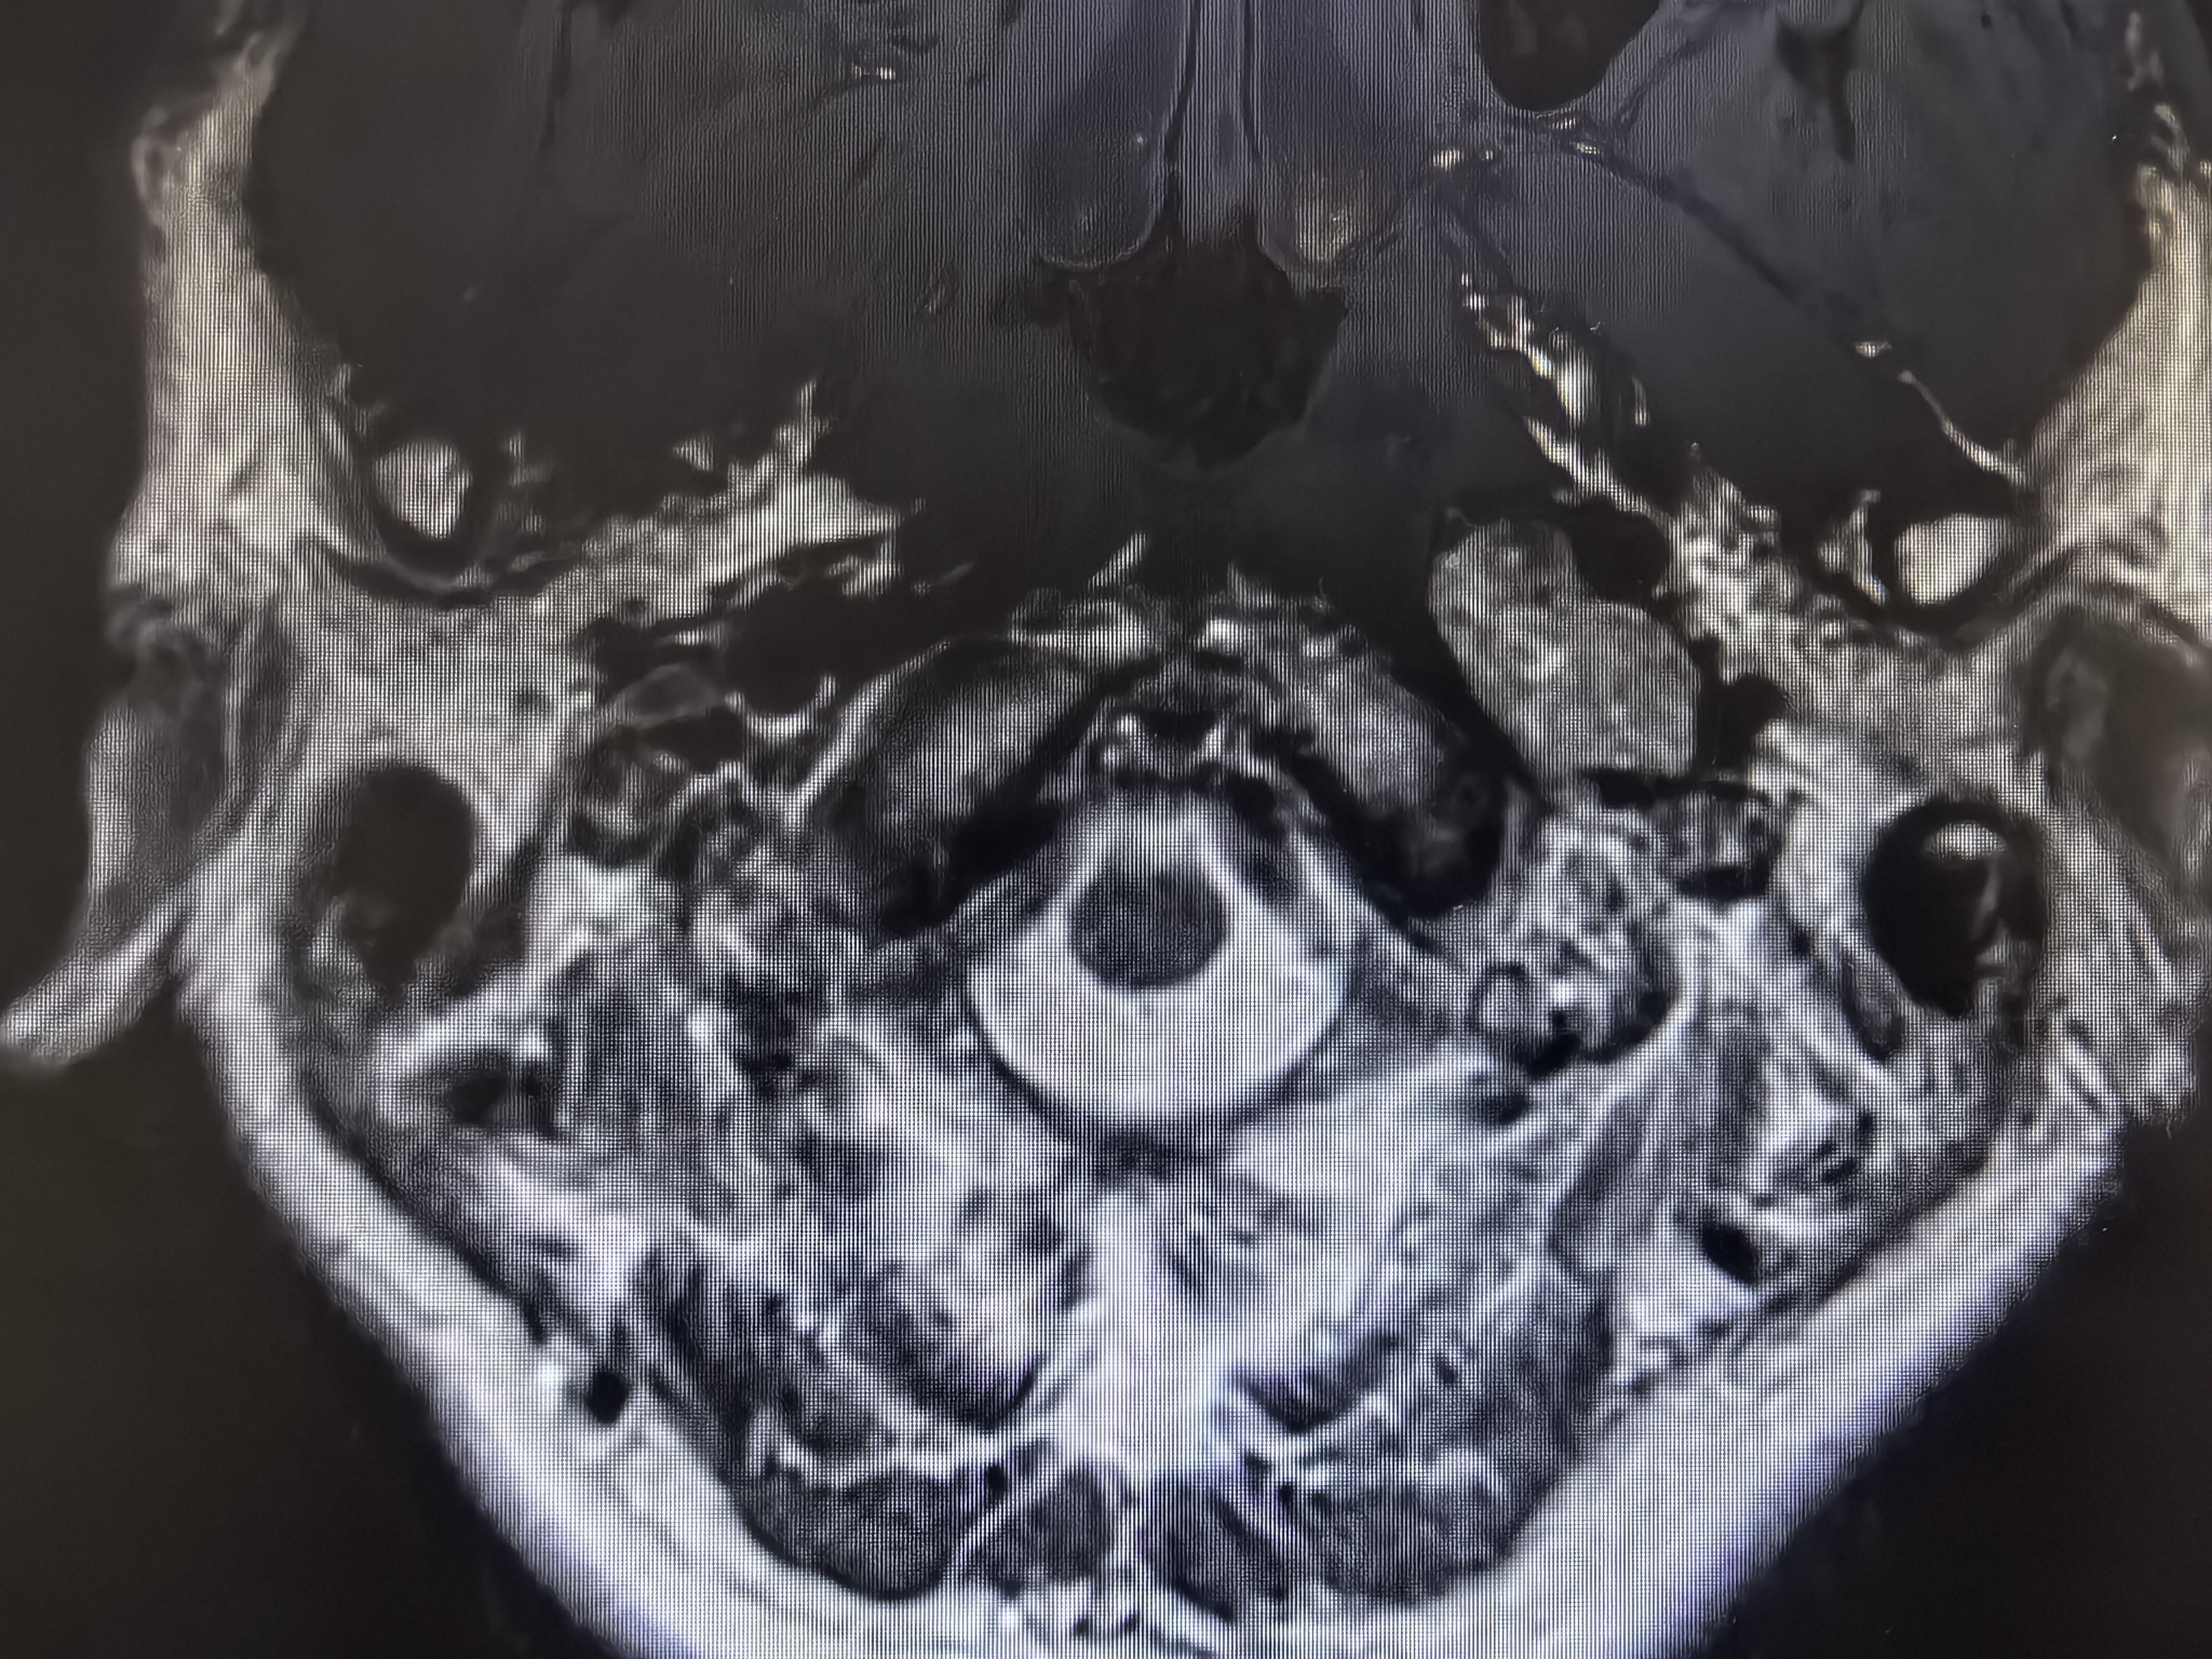

术前磁共振,显示舌下神经管扩大